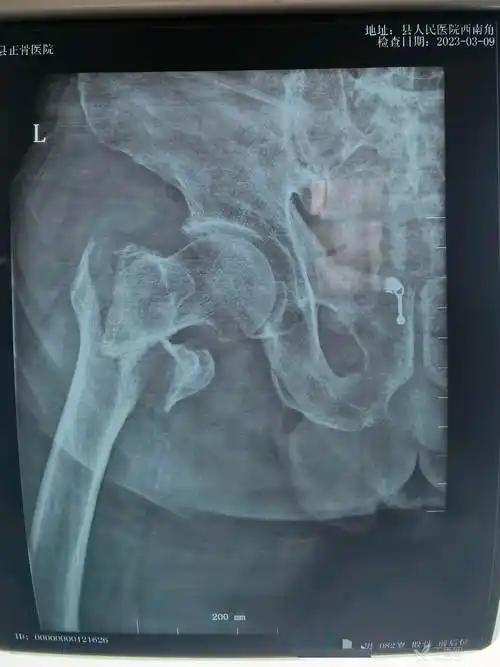

这样的一例股骨转子间骨折你会怎么复位 - 丁香园论坛